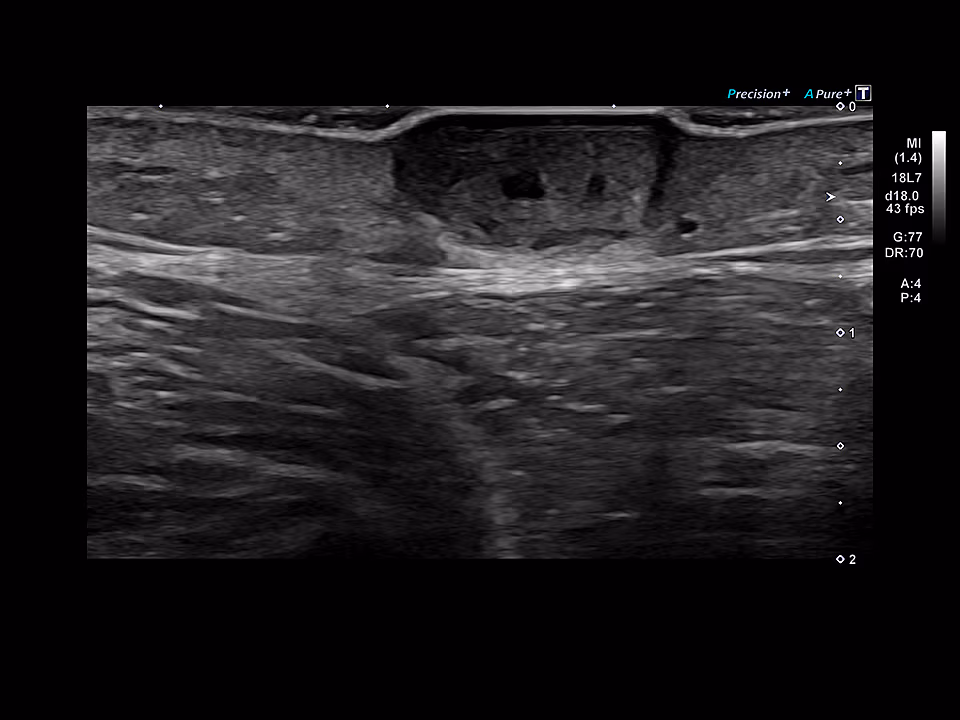

What is Color Doppler?

Color Doppler is a specialized ultrasound technique used to visualize and measure blood flow in vessels. It helps doctors evaluate circulation in arteries and veins and is commonly used in pregnancy, heart studies, and vascular conditions. In pregnancy, it can assess blood flow between the mother, placenta, and baby.

• Color Doppler studies